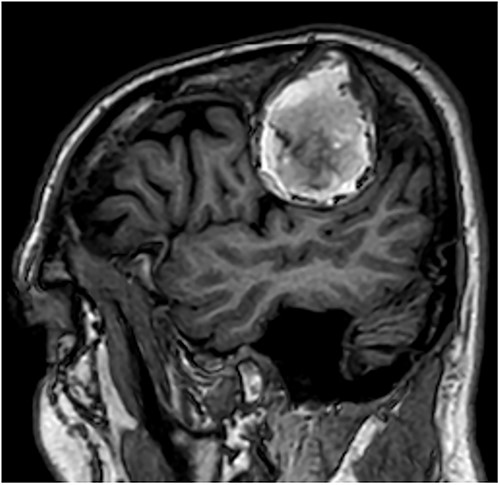

Our patient is a 76-year-old gentleman with medical history of hypertension and lumbar spondylosis. He did not have any previous history of trauma or systemic infections. He had presented to his local hospital with a 2-day history of left arm numbness. He did not report any headaches or giddiness. On clinical assessment, he did not have any neurological deficits. A CT brain and MRI brain (Figs 1–5) with contrast revealed a 53 × 53 × 41 mm partially calcified, heterogeneously enhancing conical shaped right extra-axial parietal convexity lesion. The overlying calvarial bone was remodelled and possibly eroded. There was evidence of prior haemorrhage within the lesion and scattered internal and peripheral calcification. Based on these characteristics, the possible diagnoses were that of an intraosseous meningioma, haemangioma and giant cell tumour. Patient was consented for craniotomy and excision of the tumour.

T1-weighted contrast-enhanced sagittal MRI scan showing the lesion with intralesional haemorrhagic products. There is no evidence of dural invasion.